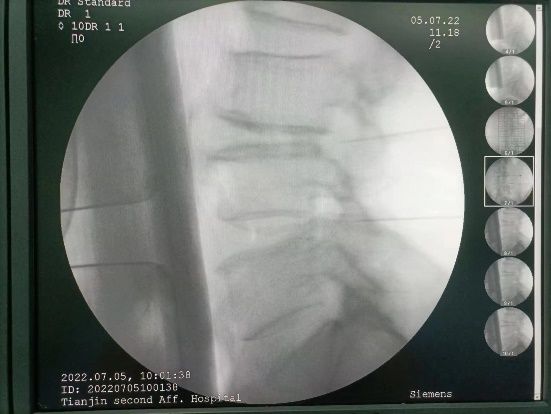

牵引治疗,采用骨盆牵引,可以增加椎间隙宽度,减少椎间盘内压,椎间盘突出部分回纳,减轻对神经根的刺激和压迫,需要专业医生指导下进行。理疗和推拿、按摩可缓解肌肉痉挛,减轻椎间盘内压力,但注意暴力推拿按摩可以导致病情加重,应慎重。